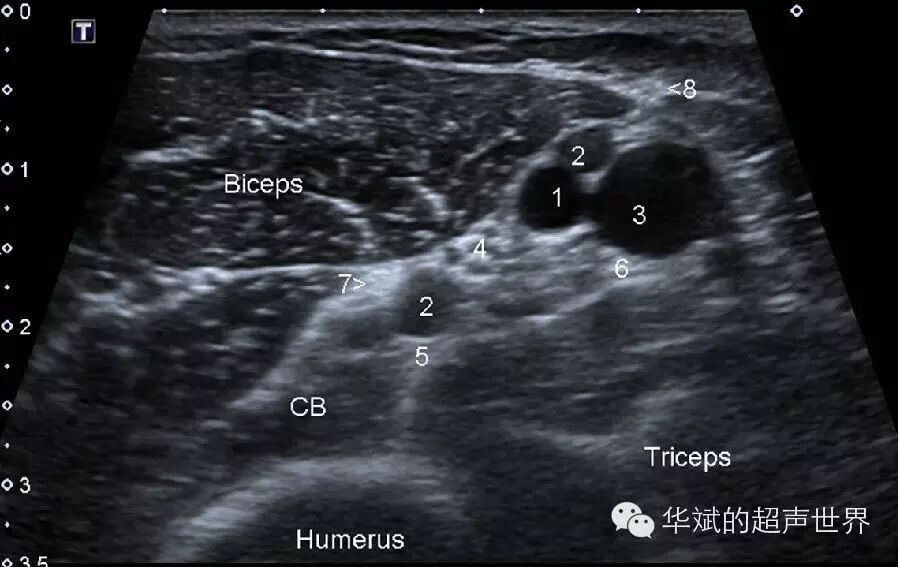

可以以血管作为标志的外周神经非常多。大部分较大的神经周围都有较大的血管伴行,这种情况下血管只是作为识别神经的辅助标志,如上臂内侧肱动脉周围的血管神经束,其中肱动脉、肱静脉和贵要静脉都是定位各条神经的重要标志(图3)。其他的例子还有:股总动静脉脉可以作为股神经的定位标志,腘动脉可以作为腘窝处胫神经的定为标志,股管内股动脉可以作为隐神经的定位标志等等。

3 上臂内侧近段肱血管神经束。Biceps:肱二头肌,Triceps:工三头肌,CB:喙肱肌,从18 分别是:肱动脉、肱静脉、贵要静脉、正中神经、桡神经、尺神经、肌皮神经和上臂内侧皮神经